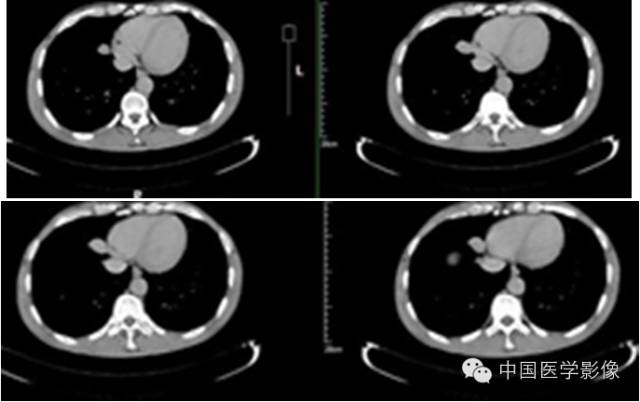

【影像资料】

平扫

动脉期

静脉期

延迟期